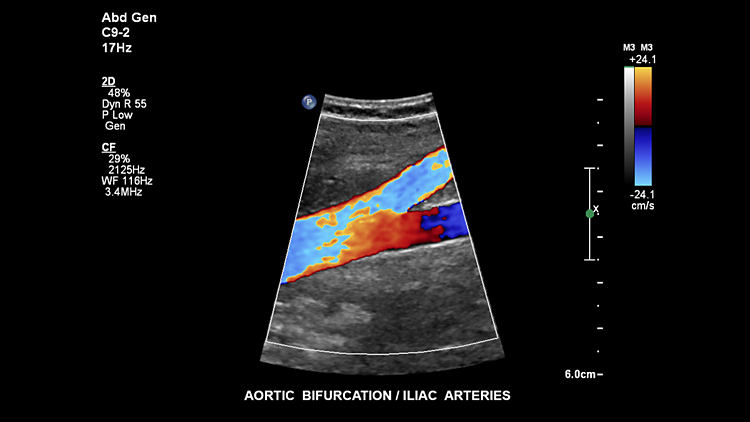

Расслоение аорты, C9-2